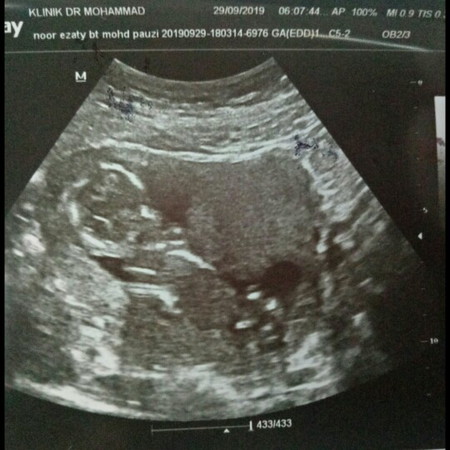

rahim ada air

semalam saja2 pegi scan, then doc bgtau perkembangan janin semua, tiba2 doc tnya ada keluar mcm air tak? saya tnya kenapa doc? doc terangkan yang rahim saya mcm byk air, sapa penah ada pengalaman mcm saya? bahaya tak kepada janin?